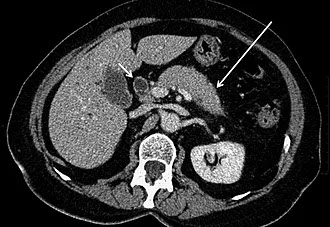

Quiste y Pseudoquiste de Páncreas

Un quiste es una cavidad cerrada y rellena de líquido, habitualmente rodeada por una membrana o cápsula.

Los quistes del páncreas pueden ser benignos, potencialmente malignos o malignos. Son poco habituales. El más frecuente (90%) es el pseudoquiste pancreático, una acumulación localizada de líquido segregado por el páncreas, rodeada de una pared fibrosa, sin revestimiento, generalmente como complicación de una pancreatitis aguda o crónica, o tras un traumatismo. Menos frecuentes (10%) son los verdaderos tumores quísticos pancreáticos.

Los principales son el cistoadenoma seroso (siempre benigno), el cistoadenoma mucinoso (potencialmente maligno), el cistoadenocarcinoma mucinoso (maligno) y el tumor mucinoso papilar intraductal (TPMI) (con distinta capacidad de malignización según su localización).